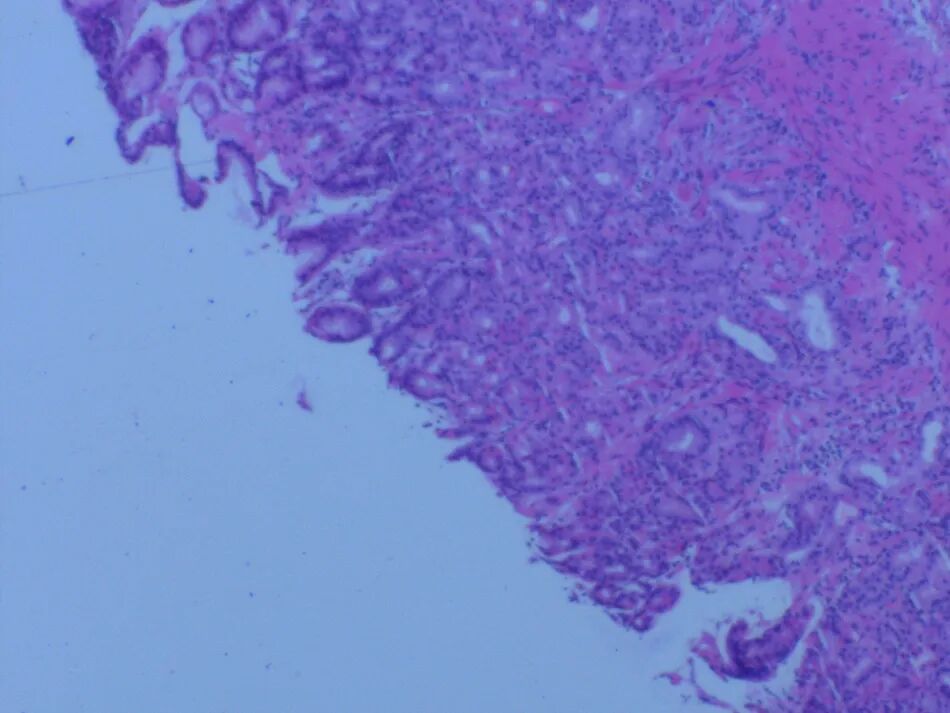

图6 胃黏膜活检示轻度慢性浅表性胃炎伴轻度急性活动性